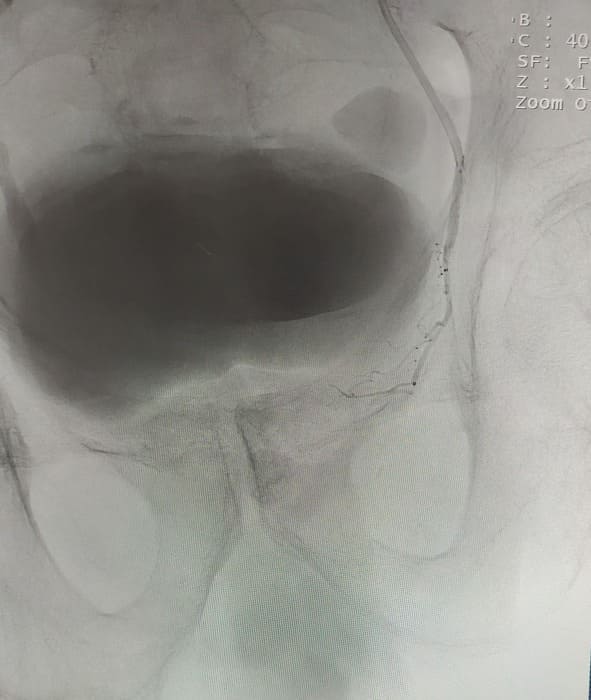

Зазвичай люди літнього віку мають вражені атеросклерозом та звивисті, внаслідок гіпертонічної хвороби судини. Цей випадок не був виключенням, тому нам довелося докласти максимум зусиль, використати високотехнологічне обладнання та інструменти, щоб віднайти цільові судини. На диво, незважаючи на попередню операцію, судинний малюнок рецидивної простати збігався з тим який буває у не оперованих пацієнтів. Тому нам вдалося їх чітко визначити з обох сторін та заповнити емболами. Це доволі кропітка праця, адже щоб викликати ішемію, необхідно поступово виключити кровоплин в усій тканині залози. Полегшувало операцію лише відсутність перетоків артерій на сусідні органи. Це дозволило нам безпечно емболізувати, не боячись негативних наслідків та ускладненнь.

Операція була виконана 28.05.2021. під місцевою анестезією, доступом через прокол в правій стегновій артерії. Вже на протязі тижня зменшилась кількість походів в туалет по маленькому (вночі до 1 разу), полегшилось сечовиділення та покращилось самопочуття хворого.

Ми все ж терпляче чекали на результати ультразвукової діагностики. І були дуже раді побачити, що за три тижні розмір залози зменшився в три рази.